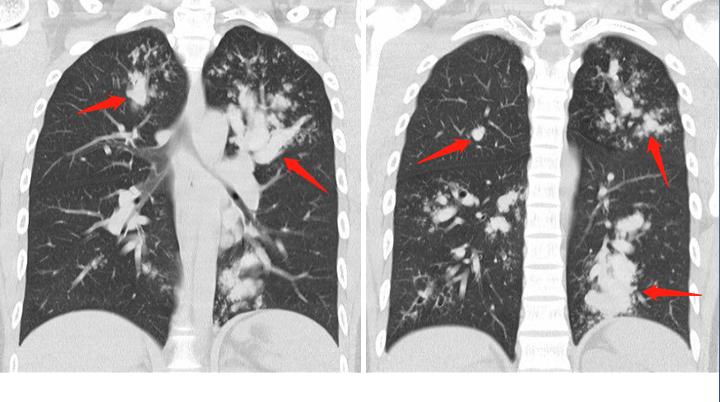

CT发现他的支气管多发扩张,箭头所示,像手指套一样白色迂曲的影子,这个叫“指套征”,周围还有一些白色小点片状浸润影,和一些小树芽征。

这种手指套样的改变,其实还可发生于肺结核、肺癌阻塞支气管等情况,为什么会直接考虑真菌感染呢?答案在下面这张图:

除了上面这些表现之外,ABPA病人的CT片还有另一个常见的典型表现:病变游走性!一处病灶吸收,过一阵子另一叶肺里又出现新病灶。

这是因为机体不同部位对吸入的霉菌孢子产生变态反应的程度和时间有差异,或者再次吸入霉菌孢子引发新的变态反应有关。